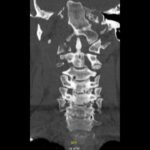

The Jefferson fracture classification system describes fractures of the atlas (first cervical vertebra or C1). Jefferson fractures with potential tears in the transverse ligament can cause cervical spine instability and can result in neurologic injury if not appropriately diagnosed and managed. We present the case of a 54-year-old man who fell head first with cervical spine tenderness and upper extremity paresthesias. The patient’s Jefferson fracture was diagnosed via computed tomography. The patient was then treated non-operatively for his Jefferson fracture, and he had an unremarkable hospitalization. Emergency physicians should obtain surgical consultation and consider the possibility of ligamentous injury in patients suffering injury to the cervical spine.